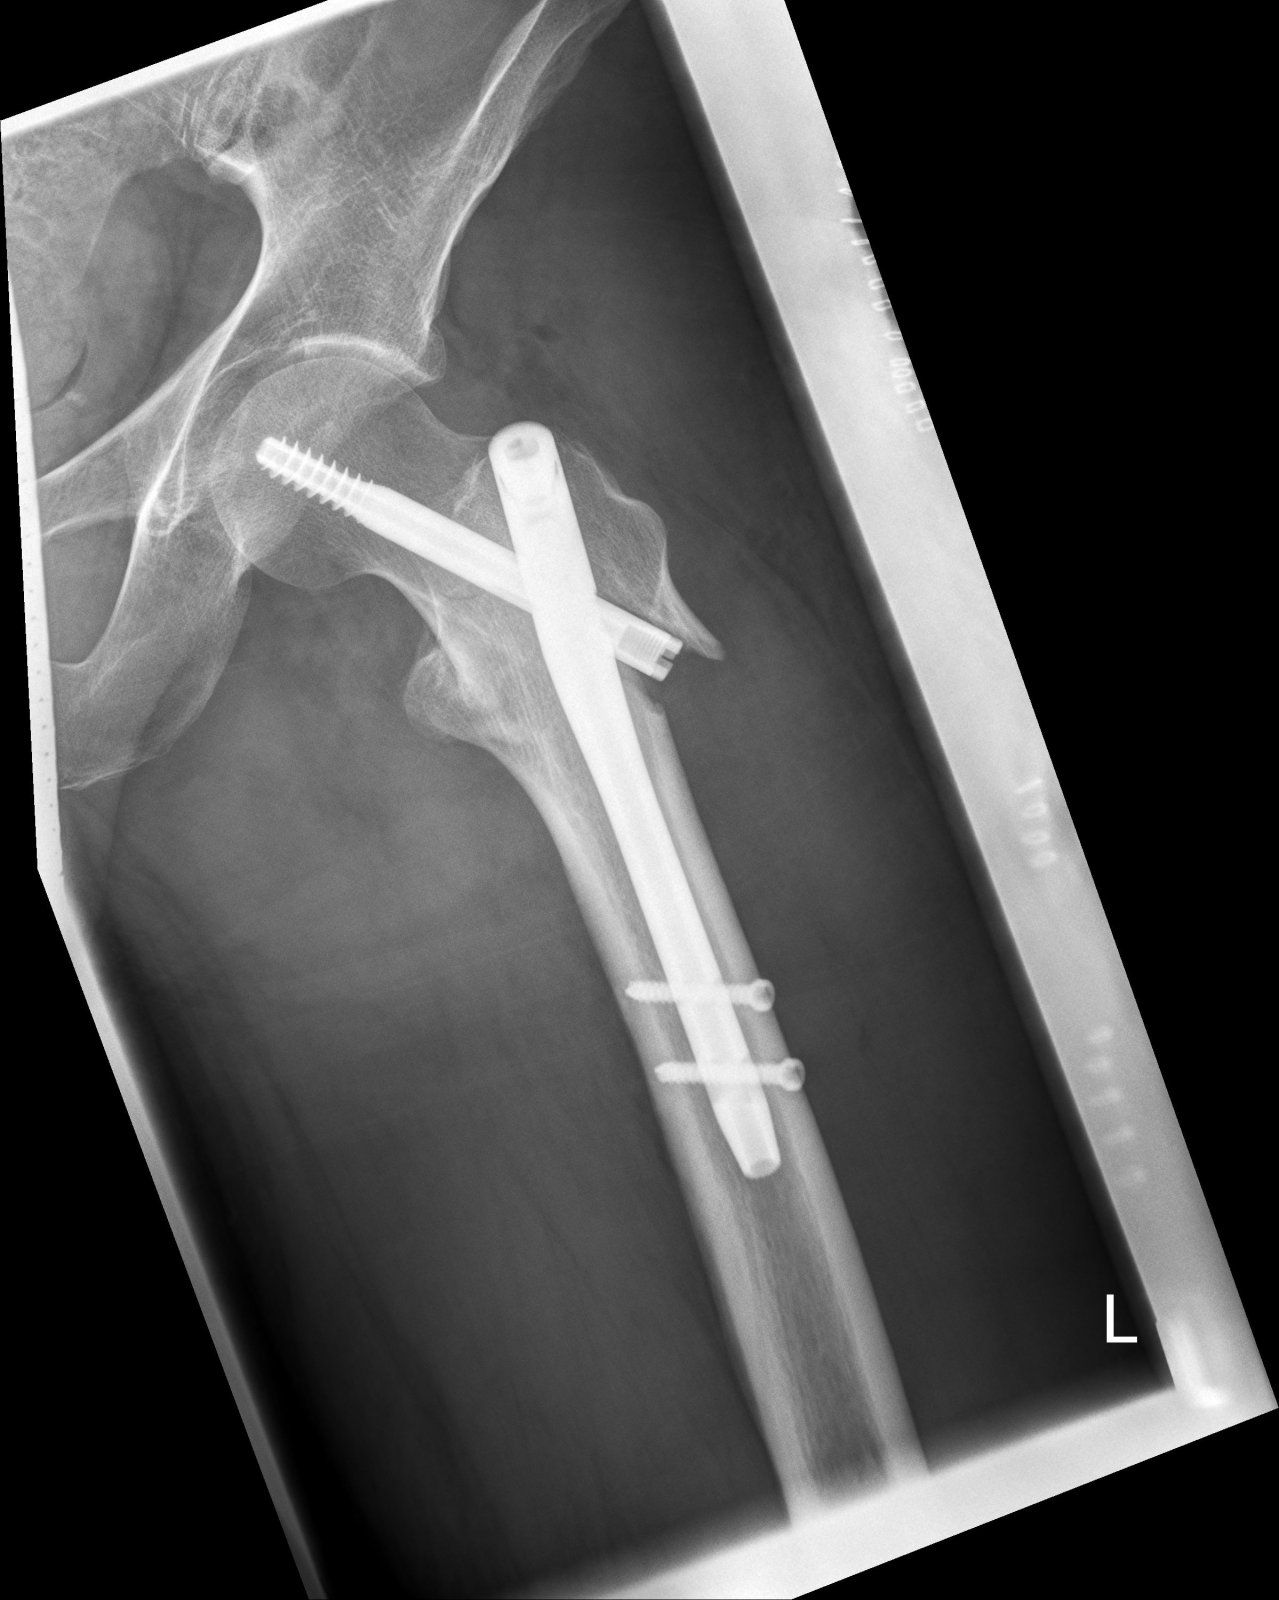

Titan ist es, darf im Körper bleiben.Puh, sieht ja heftig aus. Was verbauen die denn da so? Titan?

Zumindest mal der halbe Oberschenkel. Der Nagel ist 20cm lang, die Schraube oben 13cm. Ist schon massiv. Wie sagte ich vorhin zu meinen besten Freund: Nach meinen Tod lohnt sich das ausschlachten!Ach du meine Güte, hast du vor, langsam eine Maschine zu werden? Das halbe Bein besteht als Metall.

Jupp, bei Titan denke irgendwie an den Freilaufkörper meiner 7700 Dura Ace Nabe von 1998 ...Titan ist es, darf im Körper bleiben.

Zumindest mal der halbe Oberschenkel. Der Nagel ist 20cm lang, die Schraube oben 13cm. Ist schon massiv. Wie sagte ich vorhin zu meinen besten Freund: Nach meinen Tod lohnt sich das ausschlachten!